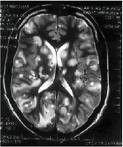

Triệu chứng có thể khác nhau tùy thuộc vào cơ quan hoặc hệ cơ quan bị nhiễm liên quan. Chẳng hạn, cá nhân đó bị ấu trùng sán lợn liên quan đến hệ thần kinh trung ương (neurocysticercosis) có thể biểu hiện triệu chứng thần kinh như rối loạn tâm thần, động kinh và thường những ca như thế dễ đưa đến tử vong.